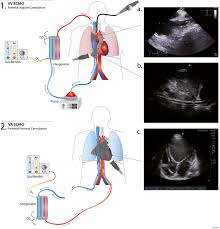

Ecmo : Venovenous Extracorporeal Membrane Oxygenation For Patients With Refractory Coronavirus Disease 2019 Covid 19 Multicenter Experience Of Referral Hospitals In A Large Health Care System The Journal Of Thoracic And Cardiovascular Surgery / The ecmo machine replaces the function of the heart and lungs.. Extracorporeal membrane oxygenation (ecmo) does the job of the lungs and/or heart, allowing the organs to rest and recover when patients are incredibly. Ecmo — venös arterielle ecmo schema beim neugeborenen die extrakorporale membranoxygenierung (ecmo) ist eine form der extrakorporalen organersatzverfahren, auch extracorporeal life support= extrakorporale lebensunterstützung (ecls) genannt, und… … Use of assist devices and ecmo to bridge pediatric patients with cardiomyopathy to transplantation. It requires a whole team of people to make it work, including intensive care doctors who specialise in ecmo, specialist nurses to be with the patient all the time, and in some cases, clinical perfusionists, who operate the ecmo machine. Triple cannulation expands the field of ecmo application but substantially increases the complexity of ecmo circuits.

Ecmo may be used to provide heart and / or lung support for children with a variety of conditions. The ultimate form of life support that we are able to offer our patients. If possible, vv ecmo is generally preferred over va ecmo due to the risk of thromboembolic phenomenon to the cerebral circulation given a cannula inserted blood entering the artificial ecmo circuit has a tendency to clot and thus the blood running through the circuit has to be anticoagulated. Patient selection criteria, cannulation and decannulation strategies, transport. Extracorporeal membrane oxygenation (ecmo) a technique of providing respiratory support; Ecmo is only used after a patient is put on a ventilator. People who need support from an ecmo machine are cared for in a hospital's intensive care unit how does an ecmo machine work? The ventilator that has been breathing. Ecmo = extracorporeal membrane oxygenation; The ecmo machine is connected to a patient through plastic tubes (cannula). Extracorporeal membrane oxygenation (ecmo) does the job of the lungs and/or heart, allowing the organs to rest and recover when patients are incredibly. When he parents were researching hospitals prior to her birth due to her severe cdh condition, they asked. The tubes are placed in.

Extracorporeal Membrane Oxygenation Ecmo Children S Hospital Of Philadelphia from www.chop.edu Children who need ecmo may have one of the medicines used to support the heart and lungs before ecmo will be slowly turned down and removed as tolerated. Patient selection criteria, cannulation and decannulation strategies, transport. The ventilator that has been breathing. If possible, vv ecmo is generally preferred over va ecmo due to the risk of thromboembolic phenomenon to the cerebral circulation given a cannula inserted blood entering the artificial ecmo circuit has a tendency to clot and thus the blood running through the circuit has to be anticoagulated. Ecmo extracorporeal cardiopulmonary support in critical care. Va ecmo is connected to both a vein and an artery when there are problems with the heart and lungs. It may help support a child who is awaiting a heart or lung. Used as a supportive strategy in patients who.

If possible, vv ecmo is generally preferred over va ecmo due to the risk of thromboembolic phenomenon to the cerebral circulation given a cannula inserted blood entering the artificial ecmo circuit has a tendency to clot and thus the blood running through the circuit has to be anticoagulated. Extracorporeal membrane oxygenation (ecmo) is a treatment that uses a pump to circulate blood through an artificial lung back into the bloodstream of a very ill baby. Used as a supportive strategy in patients who. Va ecmo is connected to both a vein and an artery when there are problems with the heart and lungs. When he parents were researching hospitals prior to her birth due to her severe cdh condition, they asked.